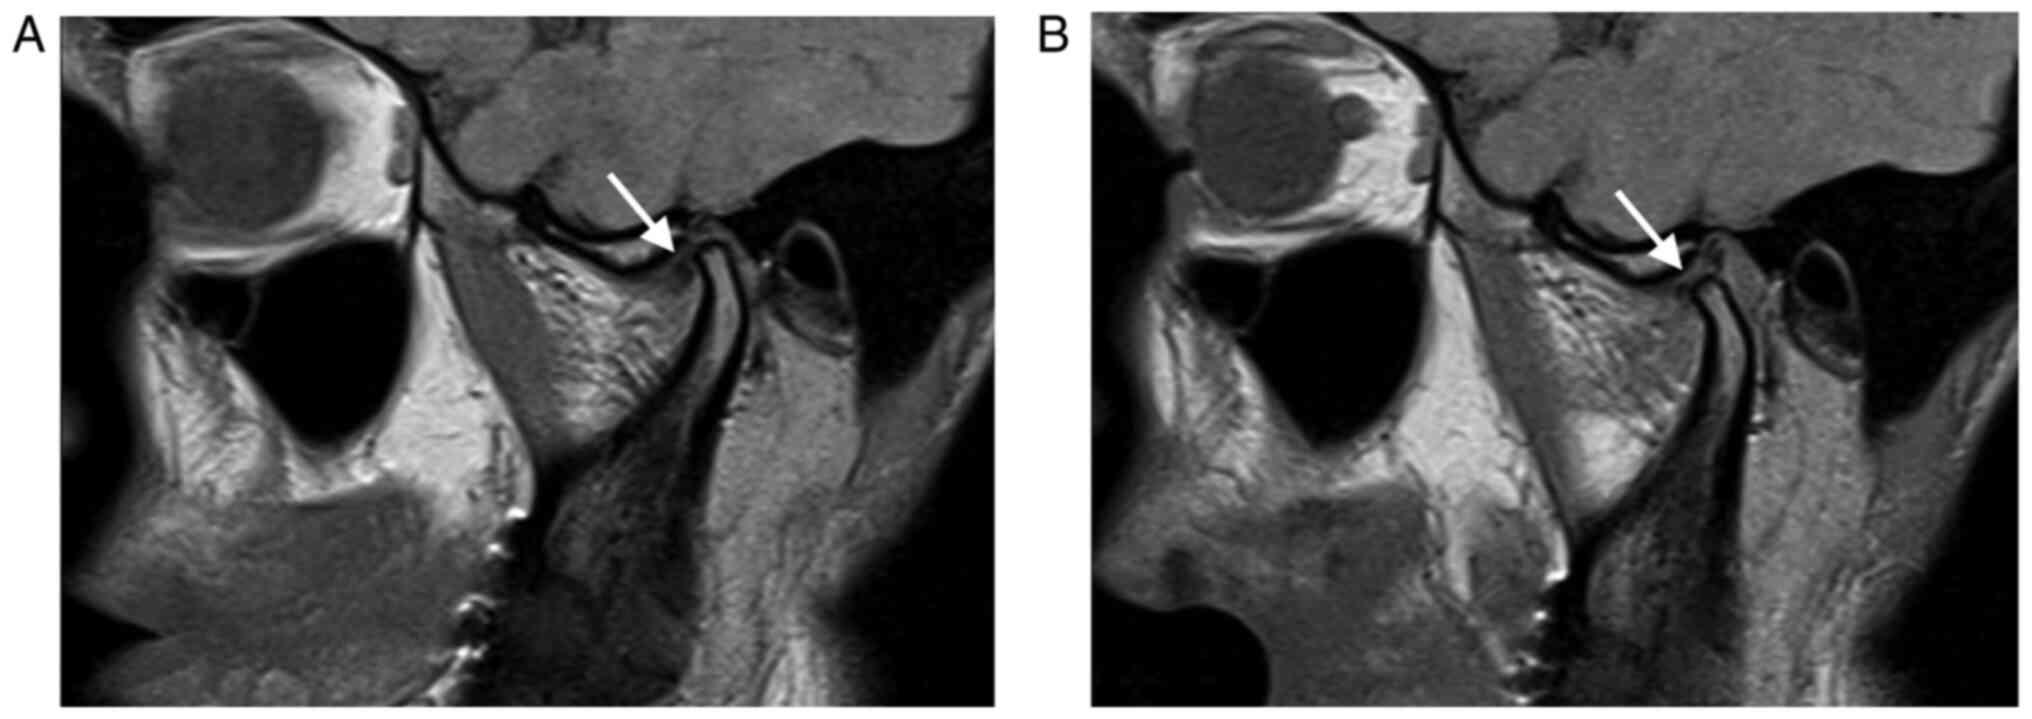

Disc displacement was considered to be present if the posterior margin of the posterior band was situated anteriorly to the vertical orientation of the condyle (the ‘12 o'clock line’) (10). The MRI examination was performed within 1-7 days following clinical examination and computerized axiography. The results were interpreted by a single specialist in maxillofacial imaging (NB; Figs. 6 and 7).

Figure 7

Sagittal proton density MRI image of an anterior disc displacement without reduction. (A) Mouth-closed. (B) Mouth-opened. Note the displaced disc (arrow) when the mouth is closed does not return to its normal position at the maximal mouth opening position.